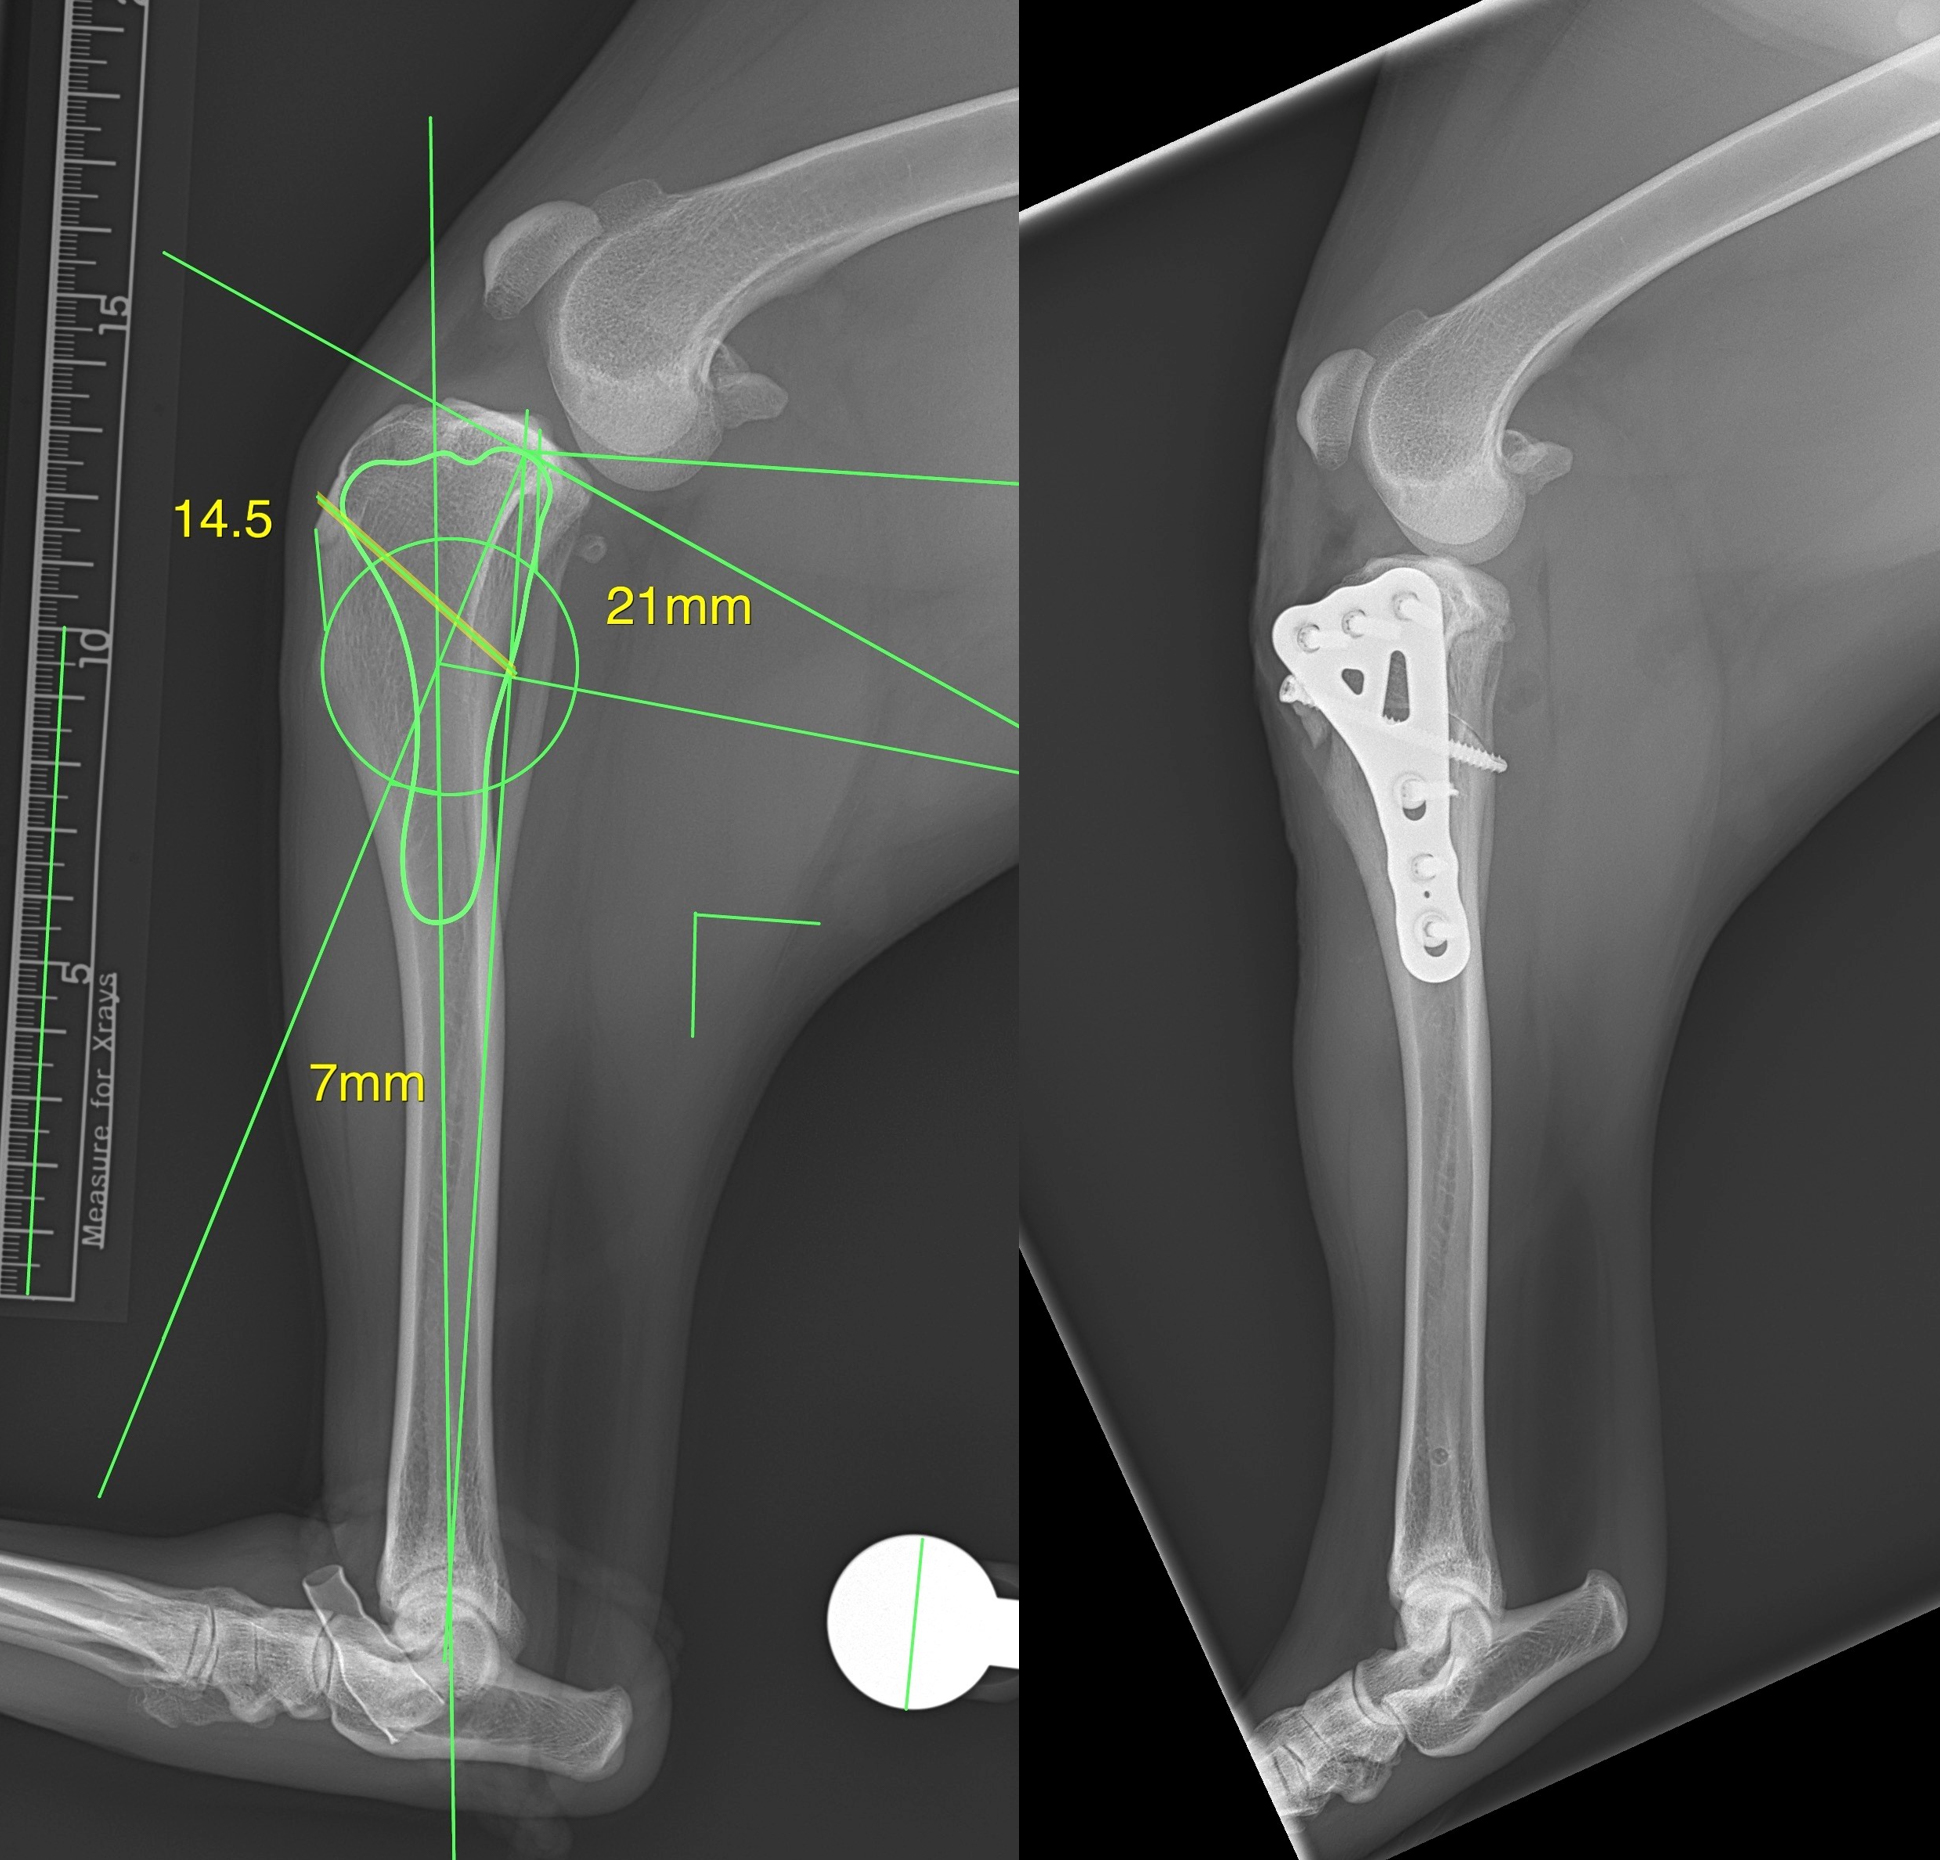

Case Description: The patient is a 35 kg dog. Following the motto "go big, go strong", a LeiLOX CBLO 3.5 mm broad plate was used for this case.

Dr. Toshi Ikeda shared his LeiLOX CBLO case with us: 1 year old Labrador, spayed, female, 30 kg. Our lightweight titanium CBLO Plate features double compression holes, limited contact to bone, and is anatomically contoured.

Here is another case from Dr. Hugo Schmökel (DVM, PhD, Dipl. ECVS, MRCVS) of a 5kg dog, featuring the LeiLOX CBLO 2.0mm locking plate.